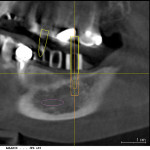

A cone-beam x-ray was taken, and the location of the mandibular nerve was mapped out (Galileos, Sirona Dental Systems). The long axis of the planned implant positions, represented by the long axis of the guide sleeve images, was evaluated in the mesio-distal and bucco-lingual planes for each site. Using the Galileos software, three virtual implants were superimposed on the x-rays to determine the appropriate size and positions for each of the three implants (Figure 4, FIgure 5, Figure 6, Figure 7, Figure 8 and Figure 9).

The treatment plan was to place three implants above the mandibular nerve without grafting or augmenting the alveolar ridge, using one implant to support each of the three missing teeth. The long axis of the diagnostic cylinders—indicating the long axis of the planned osteotomies—and the long axis of the virtual implants were determined in both the mesio-distal and bucco-lingual plane. A line was drawn through the center of the image of the diagnostic cylinders and the long axis of the virtual implants.

Analyze and Correct

In this case, the long axes of each of the three guide sleeves were analyzed in the bucco-lingual and mesio-distal planes in the cone-beam images (see Figure 4 through Figure 9), and the following corrections were made. The guide sleeve for the second bicuspid was corrected by bending the guidepost 12º in a mesio-distal plane and 15º toward the lingual in the bucco-lingual plane (see Figure 4 and Figure 5). The guidepost in the first molar position was corrected 33º to the lingual (see Figure 6 and Figure 7), and the guidepost for the second molar was corrected by bending it 30º to the lingual (see Figure 8 and Figure 9).